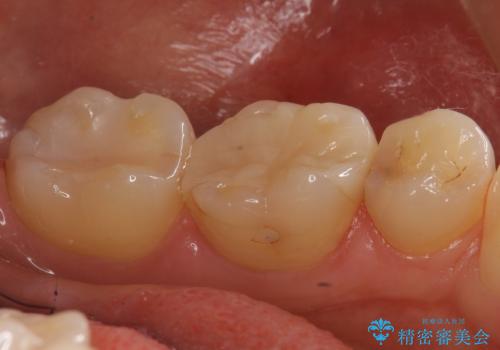

歯と歯の間の虫歯 セラミックインレーでの治療

- 矯正後の検査で歯と歯の間の虫歯が確認された患者様です。

虫歯の除去後、セラミックインレーで修復していきます。

- 右下5 セラミックインレー 77,000円費用は治療当時の料金となります

レントゲン画像からは読み取りづらいですが、視診にて歯の一部が黒く透けているのが確認できました。

小さな虫歯でも見落とさずに精度の良い修復をすることで二次う蝕のリスクを減らすことができます。